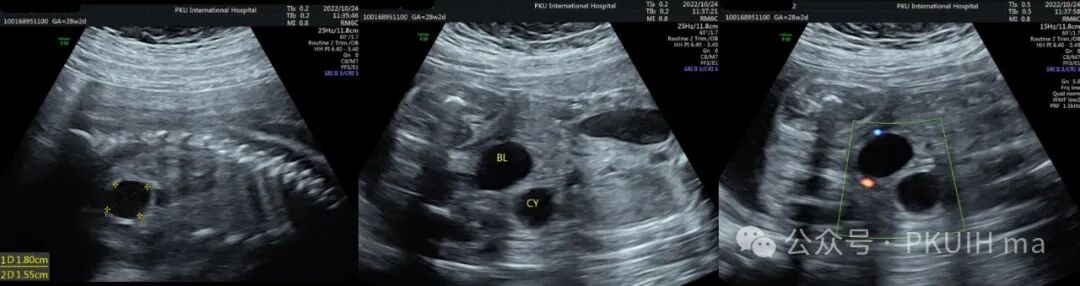

上图是一个28周发现的腹腔囊肿,在随后的观察及出生后随访中均无明显变化,生后超声提示位于肠壁外侧,初步考虑肠重复畸形或肠系膜囊肿。从产前超声图像看内壁不光滑,囊壁回声增强,可能是小肠的肠重复囊肿